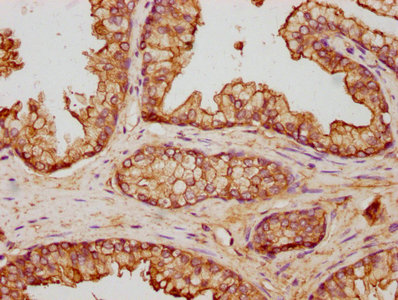

• IHC image of CSB-PA001846YA01HU diluted at 1:500 and staining in paraffin-embedded human prostate cancer performed on a Leica BondTM system. After dewaxing and hydration, antigen retrieval was mediated by high pressure in a citrate buffer (pH 6.0). Section was blocked with 10% normal goat serum 30min at RT. Then primary antibody (1% BSA) was incubated at 4°C overnight. The primary is detected by a biotinylated secondary antibody and visualized using an HRP conjugated SP system.